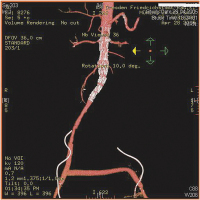

Vollbildansicht

Operationssitus

Abbildung 2: CT-Angio (Ausriss der aorto-bifemoralen Anastomosen)